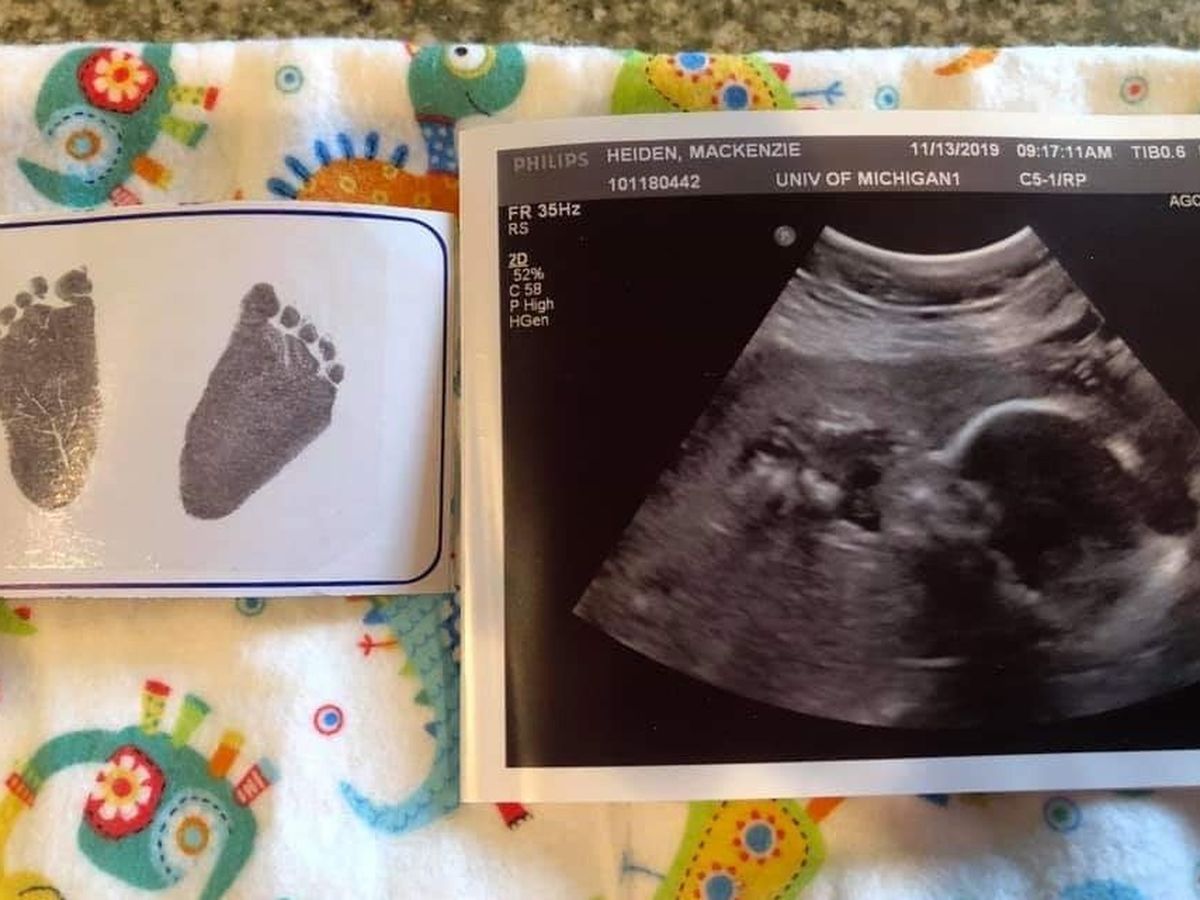

11-20-2019 Allen Michael Heiden gained his angel wings. Gerry and Mackenzie got a fatal/lethal diagnosis at their 20 week ultrasound appointment. The baby's kidneys were enlarged and filled with cysts, no kidney or bladder function which meant no amniotic fluid, very small lungs that would never develop, an enlarged heart with fluid around it, and a deformity in the back of his neck. Gerry and Mackenzie spoke with 3 different specialists that all said there was nothing that could be done for them or the baby. At this point in time they are left with large medical bills, unpayed time off work, planning a memorial service, and picking an urn for their babies ashes. I would love to be able to alleviate some of the financial stress these two are facing so they can focus on themselves and their two small boys that they have to keep going for. Please consider donating to a family that holds a very special place in so many of our hearts. If you aren't financially able to donate please keep their family in your thoughts and prayers. Thank you ❤